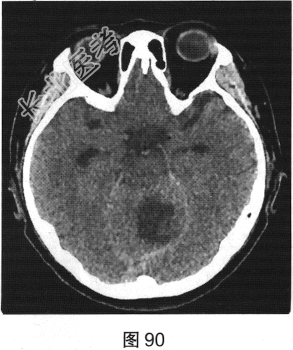

- [材料题] 患者女性,51岁,因“头晕、恶心进行性加重1个月余,伴呕吐5小时”就诊。患者于1个月前出现头晕症状,伴恶心,无视物旋转、头痛、走路不稳,无言语改变、意识障碍。患者症状反复发作并进行性加重,2周前间断出现走路不稳,似醉酒样步态,倒向左侧;5小时前出现头晕、恶心,并呕吐胃内容物,站立不稳。既往有高血压病史3年,血压控制尚可。查体:轮椅推入病房,可见步态不稳,神志清楚,应答正确,无吟诗样及爆炸样言语,遵嘱活动,双侧瞳孔等大正圆,对光反射灵敏,四肢活动可,肌力、肌张力未及异常,指鼻试验、双侧轮替试验阴性,双侧跟膝胫试验欠稳准,双侧膝反射及跟腱反射正常,双侧病理征未引出,闭目难立征不能配合。实验室检查:外周血白细胞计数15.29×109/L,中性粒细胞百分比92.1%,二氧化碳18.8mmol/L,血糖7.05mmol/L;心肌酶、凝血试验正常。

- 多项选择题2.[提示]患者行CT及MRI检查,如图90~图95所示。CT及MRI上的阳性影像学表现包括( )

A、MRI示右侧囊实性病变

C、MRI示左侧囊实性病变

E、CT示左侧低密度灶

G、CT示右侧低密度灶